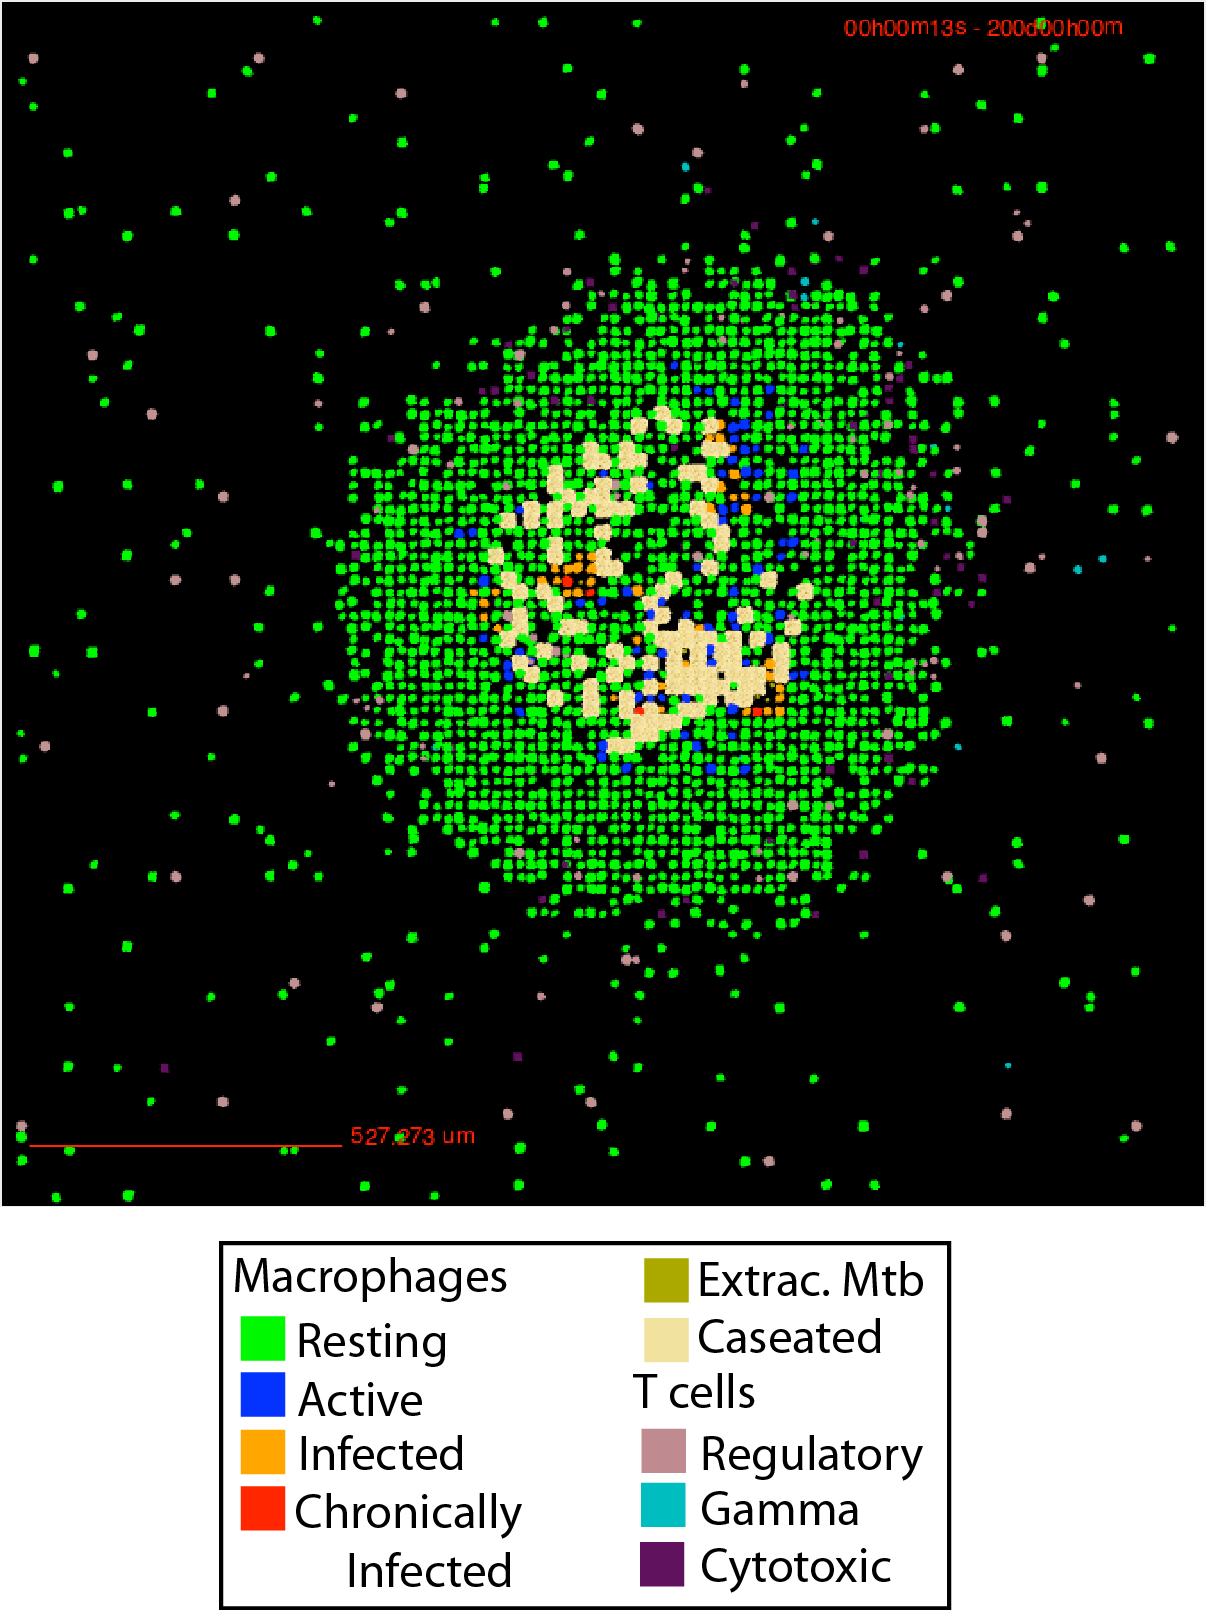

The Agent-based model (ABM) describing tuberculosis (TB) granuloma formation and function in the lung GranSim, the Agent-based model (ABM) describing tuberculosis (TB) granuloma formation and function in the lung, was developed based on four basic concepts: an environment (section of the lung parenchyma), agents (immune cells), ABM rules that govern the agents and their interactions, and the time-step (Δt) used to update events. The attached documentation illustrates the details of how each of these features have been implemented in the form of a pseudocode. The model was first published in 2004 but has been continually updated to include the latest biological information and technological advances. Example of GranSim Time Lapse Simulation 2-Dimensional Granuloma Simulator For more details on GranSim rules and specifications see the documentation file: gransimrules-v2.pdf Parameter Table for GranSim: S1_Table.louisjos-May2021.pdf For more information regarding each individual type of model we use GranSim in (multi-scale, multi-compartment, molecular details, etc) please see our individual publications on those topics at: http://malthus.micro.med.umich.edu/lab/tb.html MULTI-SCALE GranSim Multi-scale Gransim is a computational model that simulates the formation, function and treatment of tuberculosis (TB) granulomas in the lung that builds on GranSim. It is a hybrid model: ordinary differential equations describe the kinetics of molecular interactions and action of antibiotics; partial differential equations describe diffusion of molecules within the lung; an agent-based model captures the actions of individual immune cells and bacteria in a stochastic framework. The model is multi-scale, including molecular and cellular events that produce emergent behavior at the tissue scale. The framework accommodates multiple antibiotics, includes accounting of their pharmacokinetics and pharmacodynamics, and thus can predict the impact of antibiotic treatment on TB granulomas. The model is calibrated and validated against multiple datasets from non-human primates and humans. One multi-scale adaptation of GranSim is GranSim-CBM, which integrates metabolic and agent-based modeling. GranSim-CBM predicts how growth adaptations of Mycobacterium tuberculosis affects granuloma scale outcomes of infection. Antibiotic Drug Treatment in GranSim To see all PKPD equations used in GranSim, view this file: PKPD_eqns.pdf To see all PKPD code files used in GranSim, download and extract this file: GranSim-code-files.zip For a 3D version of GranSim click here.

This granuloma snapshot taken from a Non-human primate from

This granuloma snapshot taken from a Non-human primate from